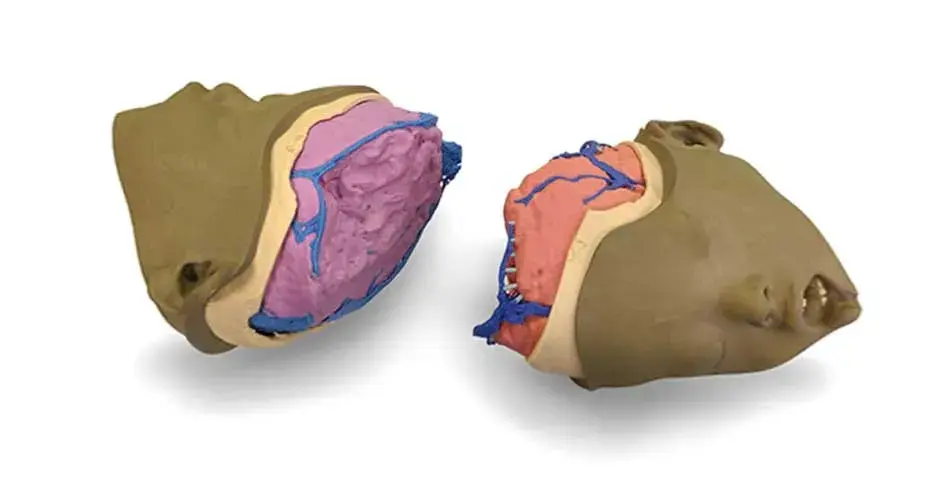

Models printed in flexible, rigid, opaque and clear materials

Translucent and opaque models printed in our high-strength materials*

Full-color anatomic models to aid in visualization of complex structures

Since each patient's anatomy is different, patient-specific anatomic models provide an opportunity to visualize and plan surgeries prior to entering the operating room. In addition, you can use anatomic models to educate patients and their families on an upcoming procedure.